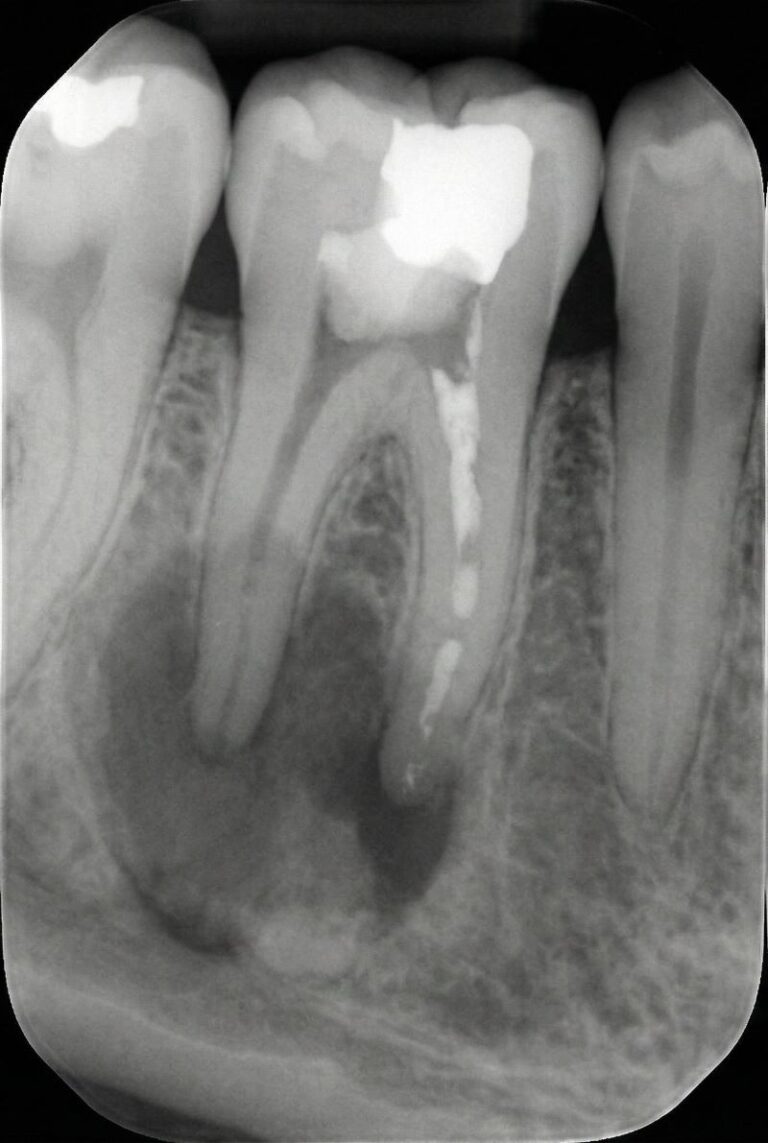

Retreatment of a root canal involves reopening the tooth, removing old gutta-percha and debris, disinfecting the canals and resealing them to eliminate persistent infection. This conservative procedure addresses hidden canals, complex root anatomy or new decay that compromised the original treatment. When standard retreatment is not enough, we may recommend an apicoectomy, which surgically removes the root tip and infected tissue through the gum.

When a first root canal doesn’t heal properly, lingering bacteria can cause pain, swelling and bone loss. Retreatment removes old filling material, cleans previously untreated or reinfected canals and reseals the tooth, helping preserve your natural root and avoid extraction or implants.

Our endodontic care includes retreatment root canals, apicoectomy (a minor procedure at the root tip) and urgent infection management. With 3-D imaging, ultrasonic cleaning and sedation, we customise treatment to your needs, comfort and budget. Patients often seek retreatment when symptoms return years after treatment, and timely evaluation can help prevent tooth loss.

You may need retreatment if pain, swelling or sensitivity returns after a root canal. X-rays showing persistent infection or bone changes also indicate the need for evaluation.

Root canals may fail due to missed canals, complex anatomy, delayed crown placement, new decay or cracks that allow bacteria to re-enter the tooth.

Retreatment cleans the tooth from inside the canal, while an apicoectomy removes infection from the root tip through a small surgical approach. Retreatment is usually considered first.